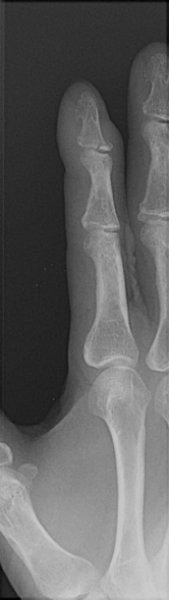

Return to Baseball Finger (Mallet Finger)